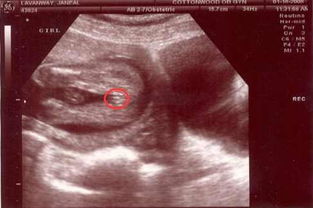

在孕16周的彩超检查中,胎儿的外形已经基本成形,四肢分明,五官初具雏形,这个阶段的彩超图能够清晰地显示胎儿的头颅、脊柱、心脏、腹部等重要器官的发育情况,是评估胎儿健康的重要手段。

值得注意的是,孕16周的彩超图中确实可以看到胎儿的生殖器官初步发育,但此时进行性别鉴定并不符合医学伦理和法律规定,我们应该更多地关注胎儿的整体发育情况,而非过早确定性别。

通过孕16周的彩超图,我们可以看到胎儿的皮肤仍然较薄,可以看到胎毛和指(趾)甲开始生长,宝宝的听力系统也在发育中,外界的声音已经开始影响到胎儿。